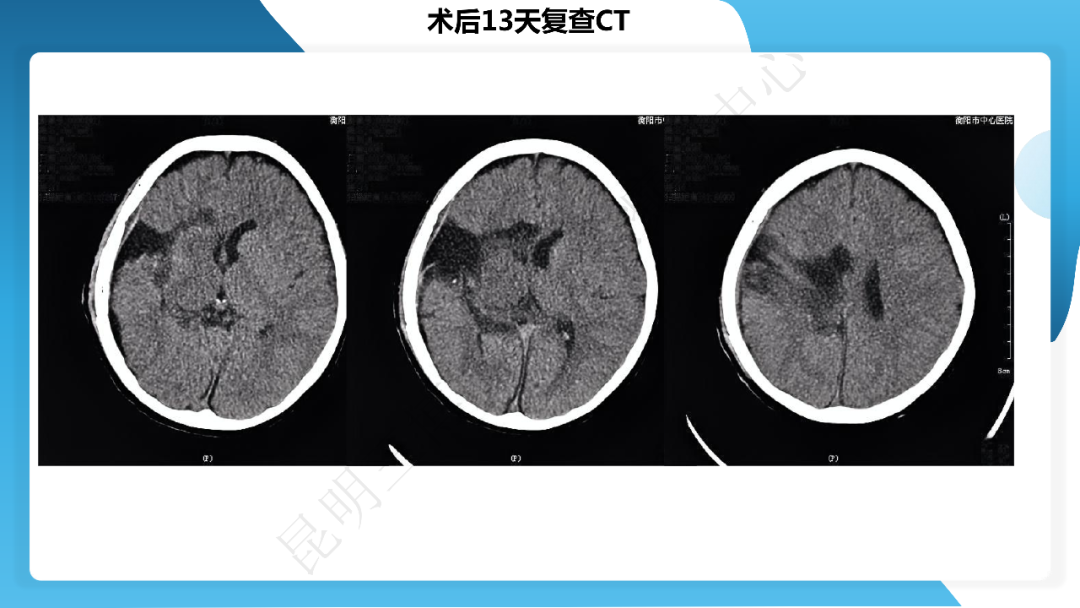

《「痫停」信步》癫痫治疗病例荟萃第四十一期---大脑半球离断术治疗 Rasmussen 脑炎引起的难治性癫痫一例